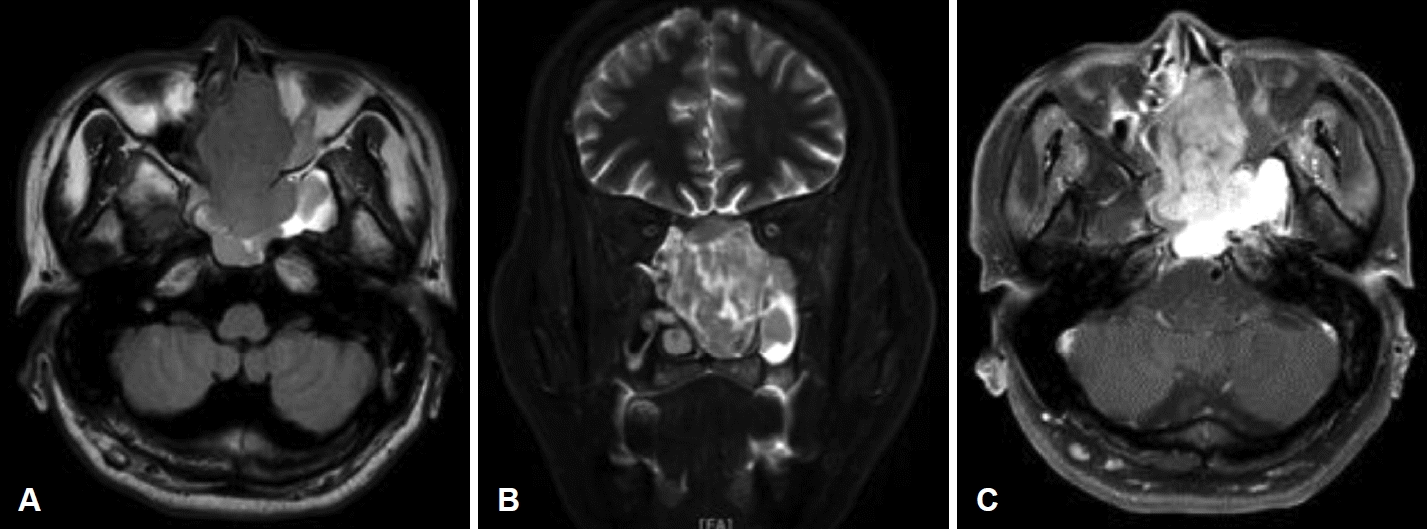

Fig. 3.

Preoperative MRI images. A and B: The mass showed hypointense on axial T1-weighted image (A) and hyperintense on coronal T2-weighted image (B). C: Axial Gd-enhanced T1-weighted image revealed heterogeneous enhancement of the mass.